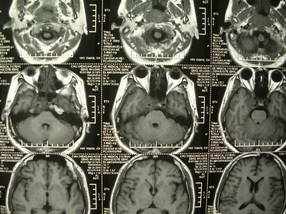

男、30、发现鼻咽部肿瘤侵犯海绵窦,未发现明显淋巴肿。请问国内那家医院治疗鼻咽部肿瘤最好?手术以何种方式为主?病灶可否全部切除?急切期待的大家的帮助。

扫描示鼻咽腔不对称,中度狭窄,右侧咽隐窝消失,局部软组织肿块,鼻咽右侧壁增厚形成肿块,突入鼻咽腔,肿块平扫呈等密度,肿块向深部侵润,右侧翼内外肌受侵,右侧咽旁间隙变窄;向后生长,头长肌界线欠清,向后上生长侵犯同侧颈动脉鞘区。双侧海绵窦增宽,内见软组织影与鼻咽部肿块相连。考虑鼻咽癌。鼻咽癌主要是放射治疗,且效果较好;到当地有治疗设备较大医院治疗即可。

这个病例有点特殊,和常见的鼻咽癌不太一样,以向颅内侵犯为主,骨质破坏区小。鼻咽癌首先要考虑,有没有其他可能?本人不会看mr片,期待有人能讲解,期待病理。